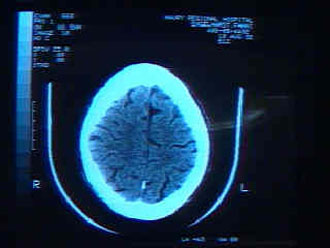

Μια απλή αιματολογική εξέταση ενδεχομένως να μπορεί, συνδυαστικά με αξονική τομογραφία εγκεφάλου, να εντοπίσει την αιτία του αιμορραγικού εγκεφαλικού επεισοδίου και έτσι να εντοπιστούν τα άτομα που διατρέχουν κίνδυνο για δεύτερο ανάλογο επεισόδιο.